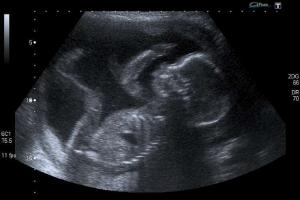

That children in the womb are alive is not a matter of scientific dispute. Leaving aside the bedrock argument that each new zygote possesses a unique genetic code, from the earliest weeks of pregnancy demonstrable signs of life in a developing baby are obvious: brain function, heartbeat, functioning nervous system are all detectable at early gestational ages.

Medical advances now mean that children can, and routinely do, survive outside the womb at ever earlier gestational ages. Birth at 26 weeks, less than two-thirds of the way through pregnancy, now comes with a near 80% chance of survival.

When Roe was decided 40 years ago, the life and rights of "un-persons" in the womb could be debated in a context that was, literally, out of sight. Today this is no longer possible. Once the discussion leaves the ultrasound screen and the delivery room, it is impossible to hide the attack on life behind the rhetoric of "women's rights."